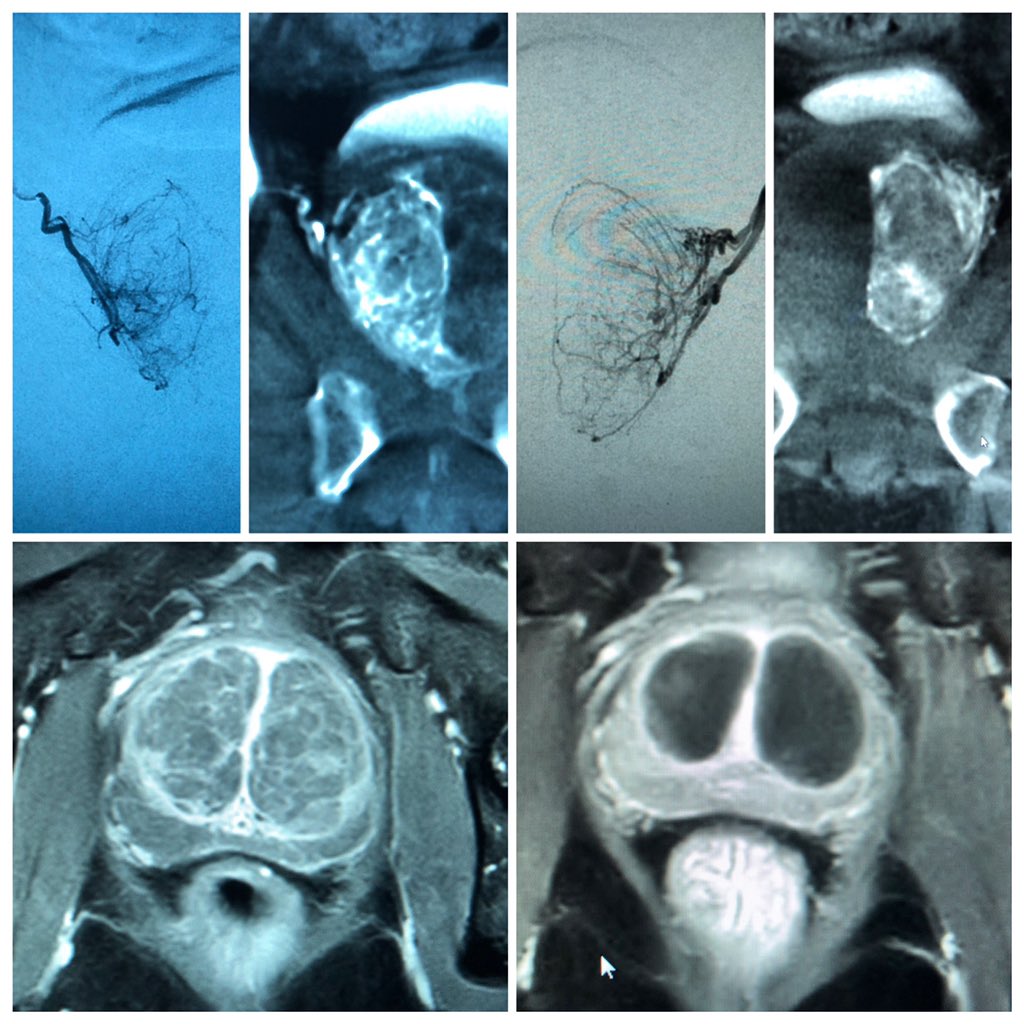

Our patient is delighted 6 months post

#PAE for#BPH with#IPSS from 27 to 3#irad helping improve quality of life and shrink the prostate from 85 to 35 grams@SIRRFS@SIRspecialists@SiemensHealth@AmerUrological@cirsesociety@GESTSymposium@InovaHealthpic.twitter.com/d6jNoa8Smx